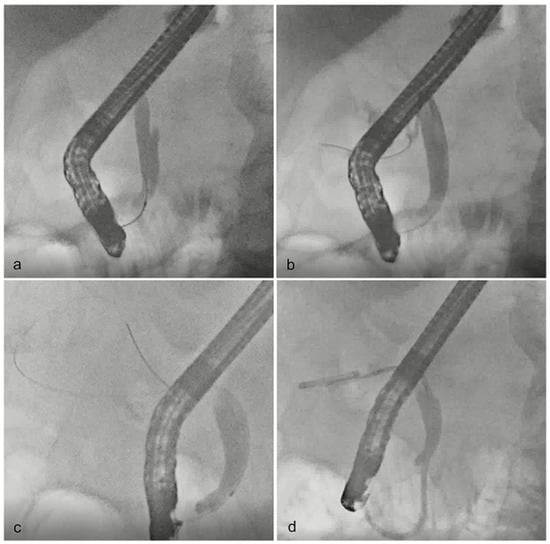

2.3. ETGBD Technique